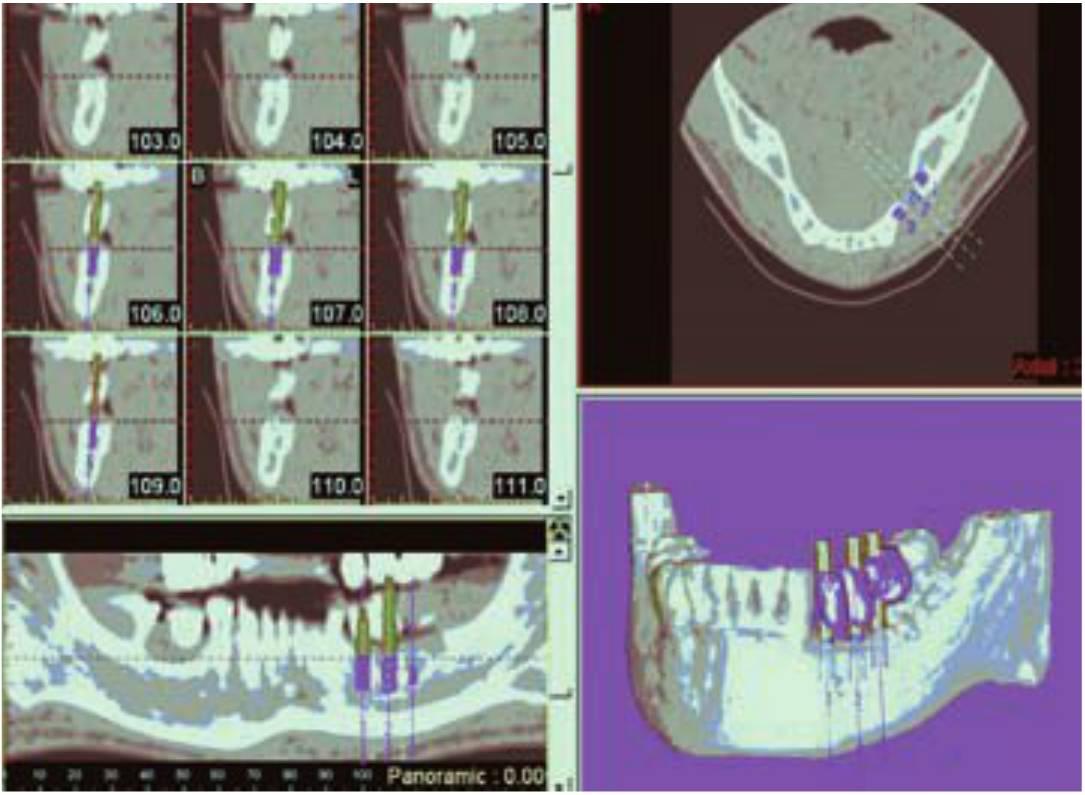

Una característica importante de la TCI es que el odontólogo y el radiólogo pueden llevar a cabo cirugía electrónica (CE) seleccionando y colocando cilindros de tamaño arbitrario que simulan la forma de la raíz de los implantes en las imágenes. Con una plantilla diagnóstica adecuadamente diseñada la CE puede llevarse a cabo para desarrollar electrónicamente la planificación del tratamiento del paciente en tres dimensiones. Los implantes electrónicos pueden colocarse en posiciones y orientaciones arbitrarias unos respecto de los otros, de los alveolos, de las estructuras críticas, y de la oclusión prospectiva y de la estética. La cirugía electrónica y la TCI permiten el desarrollo de una planificación de tratamiento en tres dimensiones que se integra en la anatomía del paciente y puede ser visualizado antes de la cirugía por miembros del equipo implantológico y el paciente para su aprobación o modificación. La TCI permite la determinación de la calidad ósea adyacente a los lechos implantológicos prospectivos (figs. 3-14 a 3-16). Una vez determinados con exactitud el número y tamaño de los implantes, junto con la densidad ósea en los sitios implantológicos propuestos, el odontólogo puede determinar con exactitud las características de los implantes antes de la cirugía.

La TCI es la técnica de imagen más exacta para la imagen implantológica y la cirugía, pero con algunas limitaciones. La ES permite la colocación de implantes electrónicos en la imagen de estudio, pero el afinamiento y la orientación relativa exacta de las posiciones de los implantes son difíciles y engorrosos de conseguir. De hecho, tres implantes consecutivos pueden requerir un paralelismo y un espaciamiento interproximal de 2,7 mm. El odontólogo puede tener que luchar para conseguir un espaciamiento y orientación relativos exactos con la ES y la TCI. En la TCI es difícil apreciar el paralelismo empleando imágenes ortogonales más que con las tridimensionales. En este caso, la orientación del implante debe ser pospuesta hasta tener la orientación desarrollada con la plantilla diagnóstica más que con la obtenida de las imágenes. La ejecución del plan puede ser difícil, una vez que se haya desarrollado el plan de tratamiento con la TCI y la ES y lo hayan aprobado el equipo implantológico y el paciente. La exactitud y precisión del plan de tratamiento obtenido con la TCI y la ES en relación con la posición de los implantes, el tamaño, la orientación, el espaciamiento relativo, la relación espacial con las estructuras críticas, la estética propuesta y la oclusión se transforman en el mayor reto en el momento de la cirugía. El plan de tratamiento puede requerir las posiciones de los implantes con una exactitud de décimas de milímetros y la orientación con un par de grados. La in formación del plan al paciente en el momento de la cirugía puede transmitirse mediante una simple visualización y comprensión por parte de un cirujano experimentado y hábil, empleando las posiciones y orientaciones obtenidas de la TCI y la ES para convertir la férula diagnóstica en una férula quirúrgica, o bien para elaborar con los datos digitales de la TCI y la ES una férula quirúrgica estereotáctica tridimensional generada por ordenador.

SurgiGuides (Materialise NV, Glen Bumie, Md.) son guías de perforación generadas por ordenador fabricadas mediante el procedimiento de estereolitografía. El concepto de SurgiGuide se basa en la planificación del tratamiento prequirúrgico empleando el programa Simplant para el posicionamiento ideal de los implantes. Estas guías con los diámetros de fresados de osteotomía quirúrgica secuenciados pueden ser osteosoportadas, dentosoportadas o mucosoportadas. Los SurgiGuides tienen tubos metálicos cilindricos que se corresponden con la preparación de osteotomía deseada y los diámetros de taladros específicos. El diámetro del tubo de perforación suele ser 0,2 mm más ancho que la fresa correspondiente, de ahí la poca probabilidad de desviar la angulación.

Los datos clínicos y los estudios han demostrado que estas guías quirúrgicas estereolitografiadas asistidas por ordenador han mostrado una mejora en la colocación del implante y que estas guías permiten una translación precisa de un plan de tratamiento predeterminado directamente al terreno quirúrgico (v. cap. 1 3).